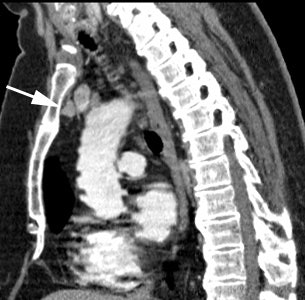

Ectopic parathyroid adenoma: The patient in the case below presented with hyperparathyroidism. A dual phase Tc-MIBI examination revealed a persistent focus of tracer accumulation in the chest (black arrows) on both early and delayed imaging. A SPECT exam was performed to better localize the abnormality which can be seen in the anterior mediastinum (click SPECT images to view cine). CT scan confirmed a soft tissue nodule in the anterior mediastinum (white arrows). At surgery, the patient was found to have an ectopic parathyroid adenoma. |